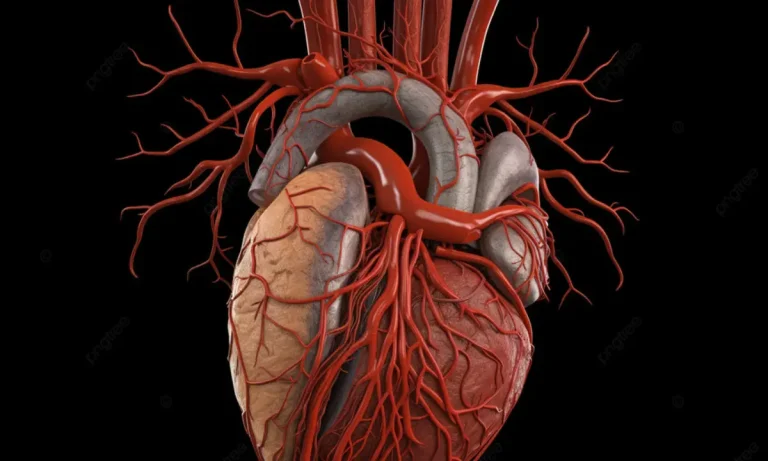

قلب، این شاهکار مهندسی بیولوژیک، نه تنها یک عضله ساده، بلکه موتور تپنده و مرکز فرماندهی سیستم گردش خون است که با هر ضربان، اکسیر حیات را به دورترین سلولهای بدن میرساند. درک آناتومی قلب انسان، کلید فهم عمیقترین فرآیندهای فیزیولوژیک و اساس دانش پزشکی مدرن است. این گزارش، با هدف ارائه یک راهنمای جامع و در عین حال قابل فهم، شما را به سفری در اعماق این اندام شگفتانگیز دعوت میکند. در این مسیر، با بررسی دقیق ساختارها، حفرهها، دریچهها و مسیرهای پیچیده خونی، آناتومی قلب به زبان ساده تشریح خواهد شد تا تصویری روشن از این پمپ حیاتی در ذهن شما شکل گیرد. ما از مفاهیم بنیادین آغاز کرده و به تدریج به جزئیات پیچیدهتر خواهیم پرداخت تا در نهایت، شناختی کامل از مرکز حیات بدن حاصل شود.

برای شناخت آناتومی قلب در بدن، ابتدا باید موقعیت دقیق آن را مشخص کنیم. قلب در محفظهای استخوانی به نام قفسه سینه، در فضای مرکزی میان دو ریه که به آن مدیاستینوم (Mediastinum) گفته میشود، قرار گرفته است. این اندام حیاتی در پشت استخوان جناغ سینه و بالای دیافراگم جای دارد و محور طولی آن به گونهای است که نوک یا اپکس (Apex) آن به سمت چپ و پایین متمایل است. همین تمایل به چپ باعث میشود که ضربان قلب در این سمت از سینه قویتر احساس شود. اندازه قلب هر فرد تقریباً معادل مشت گرهکرده اوست و وزن آن در بزرگسالان بهطور متوسط بین 250 تا 350 گرم متغیر است.

دیواره قلب یک ساختار عضلانی پیچیده است که از سه لایه مجزا تشکیل شده است. این لایهها از خارج به داخل عبارتند از اپیکارد، میوکارد و اندوکارد. هر یک از این لایهها دارای ساختار و عملکرد منحصربهفردی هستند که در مجموع، قابلیت پمپاژ قدرتمند و بیوقفه قلب را ممکن میسازند. در ادامه، به بررسی دقیقتر هر یک از این لایهها خواهیم پرداخت.

اپیکارد (Epicardium) که همان ورقه احشایی پریکارد سروزی است، خارجیترین لایه دیواره قلب را تشکیل میدهد. این لایه نازک و شفاف، علاوه بر نقش محافظتی، حاوی بافت چربی و همچنین عروق خونی کرونری است که وظیفه خونرسانی به خود عضله قلب را بر عهده دارند.

آناتومی قلب انسان بر پایه یک ساختار چهار حفرهای استوار است که به طور مؤثر آن را به دو پمپ مجزا تقسیم میکند: پمپ سمت راست و پمپ سمت چپ. این دو پمپ توسط یک دیواره عضلانی ضخیم به نام سپتوم از یکدیگر جدا شدهاند. هر پمپ شامل یک حفره دریافتکننده خون در بالا به نام دهلیز (Atrium) و یک حفره پمپکننده خون در پایین به نام بطن (Ventricle) است. سمت راست قلب مسئول مدیریت خون کماکسیژن بازگشتی از بدن است، در حالی که سمت چپ قلب خون غنی از اکسیژن را از ریهها دریافت کرده و به سراسر بدن پمپ میکند.

عروق کرونری